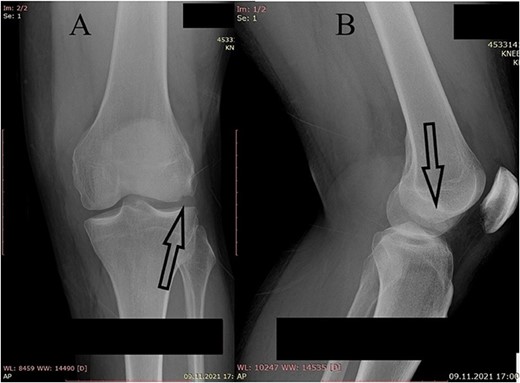

A plain X-ray of the left knee revealed a single defect of the lateral femoral condyle in the anteroposterior (AP) view. The lateral view showed a free bone fragment with a defect (Fig. 1A and B). Additional diagnostic imaging was performed. A computerized tomography (CT) scan revealed multifragmentary (three fragments) fracture of the lateral femoral condyle accompanied by a fracture of the left patella (Fig. 2). The fracture was classified as 33B3.2 according to the Association for Osteosynthesis–Orthopaedic Trauma Association (AO/OTA), Type II C (according to Letenneur) [2]. It was decided that single-approach surgery (posterior or anterior) would be insufficient for acceptable anatomic reduction and proper fixation of all the fragments because of the fracture complexity. The preoperative plan consisted of a posterior-first approach (extended posterior approach to the proximal tibia) for fixation of the largest (posterior) fragment (Fig. 3) followed by an arthroscopic anterior approach (for anterior fragment fixation). The predetermined time interval between the two procedures was to allow the healing of the joint capsule after the index surgery. Operative fixation of the patellar fracture was not indicated.

CT scan of the left knee (sagittal) focusing on the largest posterior fragment (arrow).